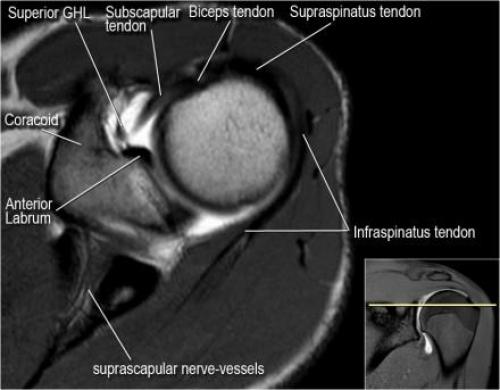

Хилл-Сакса мрт. Нормальная анатомия плечевого сустава в аксиальных изображениях и контрольный список.

- поищите os acromiale, акромиальную кость (добавочная кость, расположенная у акромиона)

- обратите внимание что ход сухожилия надостной мышцы параллелен оси мышцы (это не всегда так)

- обратите внимание что ход сухожилия длинной головки двуглавой мышцы в области прикрепления направлен на 12 часов. Область прикрепления может быть различной ширины.

- обратите внимание на верхние отделы суставной губы и прикрепление верхней плече-лопаточной связки. На данном уровне ищется SLAP-повреждение (Superior Labrum Anterior to Posterior) и варианты строения в виде отверстия под сутавной губой (sublabral foramen - подгубное отверстие). На этом же уровне по задне-боковой поверхности головки плечевой кости визуализируются повреждение Хилл-Сакса.

- волокна сухожилия подлопаточной мышцы, создавая бицепитальную борозду, удерживают сухожилие длинной головки двуглавой мышцы. Изучите хрящи.